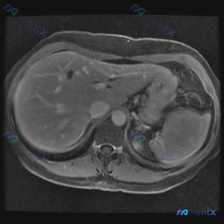

看到一份腹部MRI的影像分析,最初的问题是关于“脾脏病变”,但看完整个片子,觉得这远不止是脾脏的问题。整理了一下思路,和大家分享。 先看影像里的核心发现 这是一份腹部MRI-T2序列冠状位的影像: 1. 肝脏:形态不对,边缘是波浪状/结节状的(提示肝硬化);肝实质里有很多树枝状的高信号,是扩张的肝内...

今天看到一个影像读片的病例,用户一开始问的是“脾脏病变”,但看完图和分析后,觉得挺有警示意义的——先别被预设的问题带偏,先看客观影像事实。 整理一下这个病例的完整信息和分析思路: --- 一、先看影像事实(腹部MRI T1轴位) 1. 预设关注的脾脏 脾脏的表现其实很“干净”:形态正常,信号均匀,没...